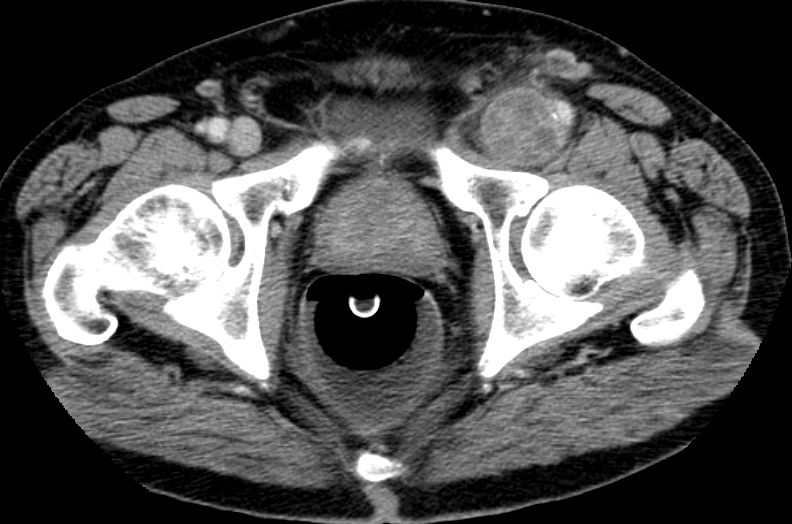

| Leiste | 72-jähriger Landwirt mit einem Leiomyosarkom der linken Leiste pT2b pN0 G2 R0. 110 x 50 x 50 mm großer, solider Tumor mit enger Lagebeziehung zum Gefäßbündel.

Infiltration des Musculus rektus abdominis.![]() |